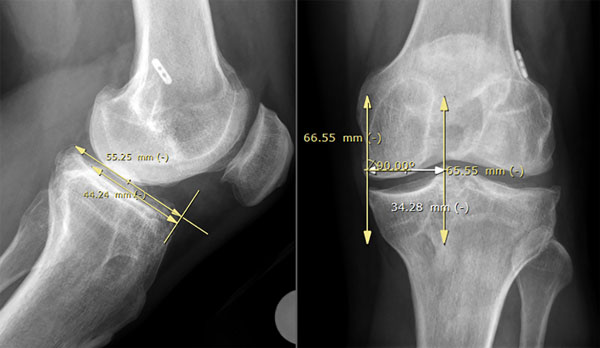

El tamaño meniscal a trasplantar se midió con el método radiográfico descripto por Pollard. El ancho se determinó utilizando la radiografía anteroposterior para medir la distancia entre el extremo anterior de la eminencia tibial y la periferia de la metáfisis tibial, y la longitud en una proyección lateral, midiendo el 80% de la longitud sagital de la meseta tibial, así como en cortes axiales tomográficos11 (figs. 4 y 5).

Figura 4: Método radiográfico de Pollard para determinar el tamaño del trasplante meniscal alogénico.

Figura 5: Medición del tamaño del TAM en corte axial tomográfico del platillo tibial.